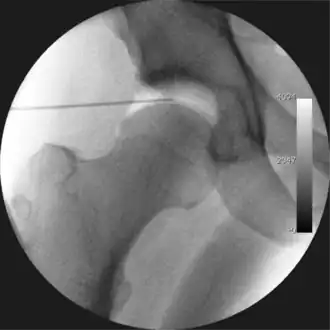

Figure 3. Fluoroscopic picture showing a mild amount of distraction of the hip before insertion of any instruments -

The procedure is performed with the patient asleep (general anaesthetic) or under spinal anaesthesia. There are two widely used methods, one with the patient on their back (supine) and the other on their side (lateral decubitus). Which is used is down to the surgeon's preference. To gain access to the central compartment of the hip joint (between the ball and socket), traction is applied to the affected leg after placing the foot into a special boot. (See fig. 2) There is specifically designed equipment for this, although some surgeons use a 'traction table', initially designed to help in the operative fixation of broken thigh and lower leg bones. The amount of traction (or pull) needed is assessed with the help of fluoroscopy (low-dose portable x-ray). (See fig. 3) It is usually not possible to distract the ball from the socket with traction alone by more than a few millimetres. Once the surgeon is happy that they will be able to gain access to the hip joint (i.e. the ball will distract from the socket by a small amount), the patient is then painted with antiseptic and the surgical drapes applied.

The next step is to insert a fine needle under x-ray guidance into the hip joint. This breaks the 'suction seal' of the joint and allows further distraction if necessary (see fig 4). The surgeon wishes to see the ball move out the socket by approximately 1 cm, so that access to the hip joint can be achieved with minimal risk of damage to the joint surfaces. Most surgeons will inject fluid into the joint at this stage, again to ensure that there is enough space between the ball and socket for safe instrument access. This needle is then removed. The next step is placement of the 'portals', or the small holes made to pass instruments into the joint. This is achieved by again passing a fresh hollow needle into the joint under x-ray control, usually in a slightly different position. The reason for this is so the surgeon can ensure that the needle, and subsequent cannulae do not penetrate and damage the acetabular labrum or cartilage joint surfaces (see fig. 5). Again, surgeons will have their own preferences as to their preferred placement. Through this hollow needle, a long thin flexible guide wire is passed into the joint, and the needle is removed over it, leaving the guide wire in situ. A small cut in the skin is made around the wire, to allow for larger cannulae to be placed over the wire through the portal. The wire therefore guides the larger cannulae into the joint. The most common external diameters of cannulae used are between 4.5 and 5.5 mm. Once the surgeon is satisfied that the cannula is in the correct position, by a combination of feel and x-ray guidance, the guide wire can be withdrawn. Once the first portal is correctly placed, any further portals may be created once the camera is in position, to ensure that they are placed with minimal risk to the joint surfaces. This process can be repeated to gain as many points of entry to the hip joint as the surgeon requires, normally between two and four. Certain of these entry points will be used for the viewing arthroscope and others for operating instruments.